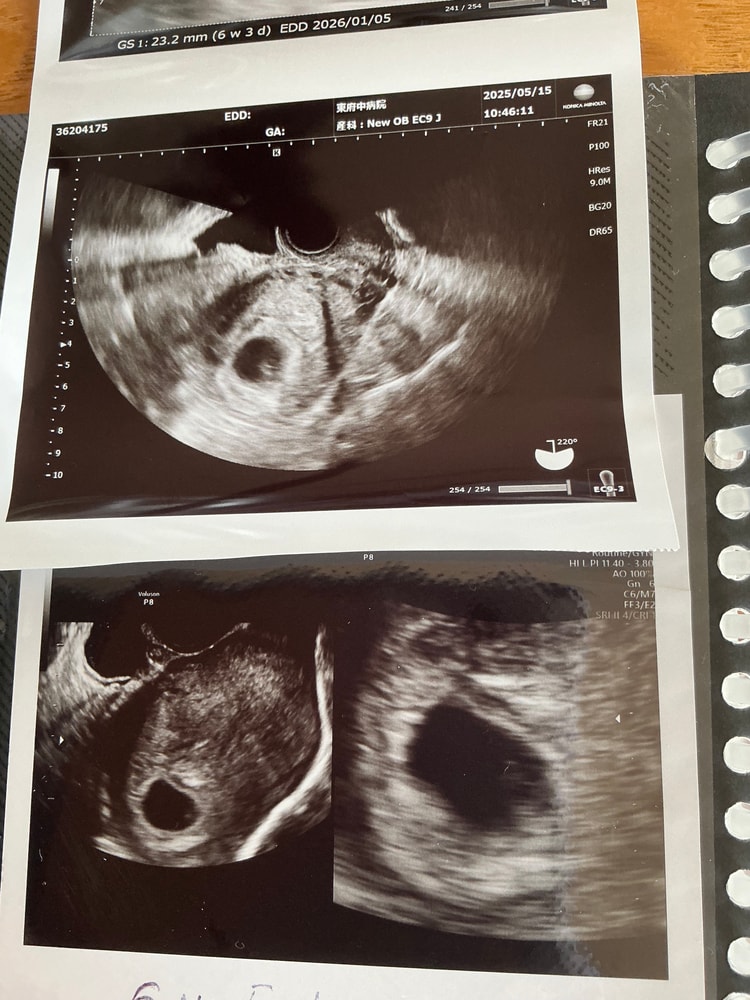

на сроке 5 недель 2 дня нашли в области матки плодное яйцо без эмбриона, размер не измеряли. На сроке 6 недель 5 дней врач увидел эмбрион и пульсацию ( ктр и размер плодного яйца не измерили, сердцебиение не удалось прослушать, врач сказал, главное, что есть пульсация) и назначил прием через две недели. Я распериживалась, уговорила себя, что все будет хорошо , и решила сегодня сходить на прием в другую клинику , хотя прошло всего 3 дня . Сегодня на приеме заменили размер плодного яйца -23мм, ктр не измеряли, но примерно 3 мм, про сердцебиение врач ничего не говорил.хотя визуально кажется , что эмбрион подрос ( сверху новое , снизу старое , разница два дня) . На повторный прием в понедельник .